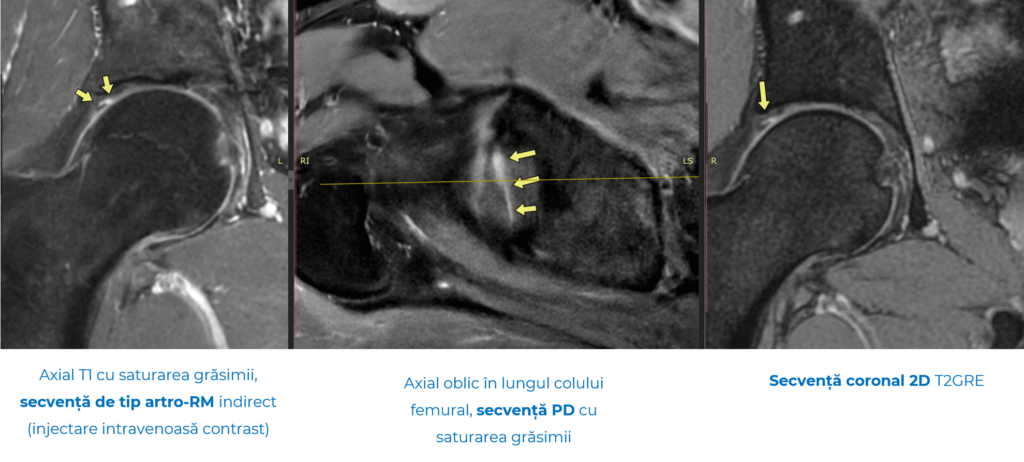

FAI este greu de observat pe radiografii simple și, adesea, necesită secvențe RMN speciale sau chiar artro-RM (RMN cu substanță de contrast intravenoasă).

- Artro-RMN-ul (rezonanță magnetică cu substanță de contrast) – aduce un plus de acuratețe în depistarea rupturilor de labrum și a leziunilor de cartilaj.

- Secvențe dedicate sistemului musculo-scheletal, printre care și secvența ZTE – tehnologie RMN disponibilă în prezent, în România, doar la Spitalul MONZA. Aceasta permite obținerea unor imagini comparabile cu cele de la CT, dar fără radiațiile asociate tomografiei computerizate. Practic, pacienții beneficiază de avantajele ambelor metode – detalii osoase de înaltă rezoluție și siguranța RMN-ului.

Secvența ZTE aduce un avantaj major în diagnosticul impingementului femuro-acetabular, unde modificările osoase fine fac diferența. În combinație cu RMN-ul convențional și artro-RMN-ul, permite o evaluare completă: os, labrum și cartilaj. Această abordare integrată oferă un diagnostic mai precis și un plan terapeutic personalizat.